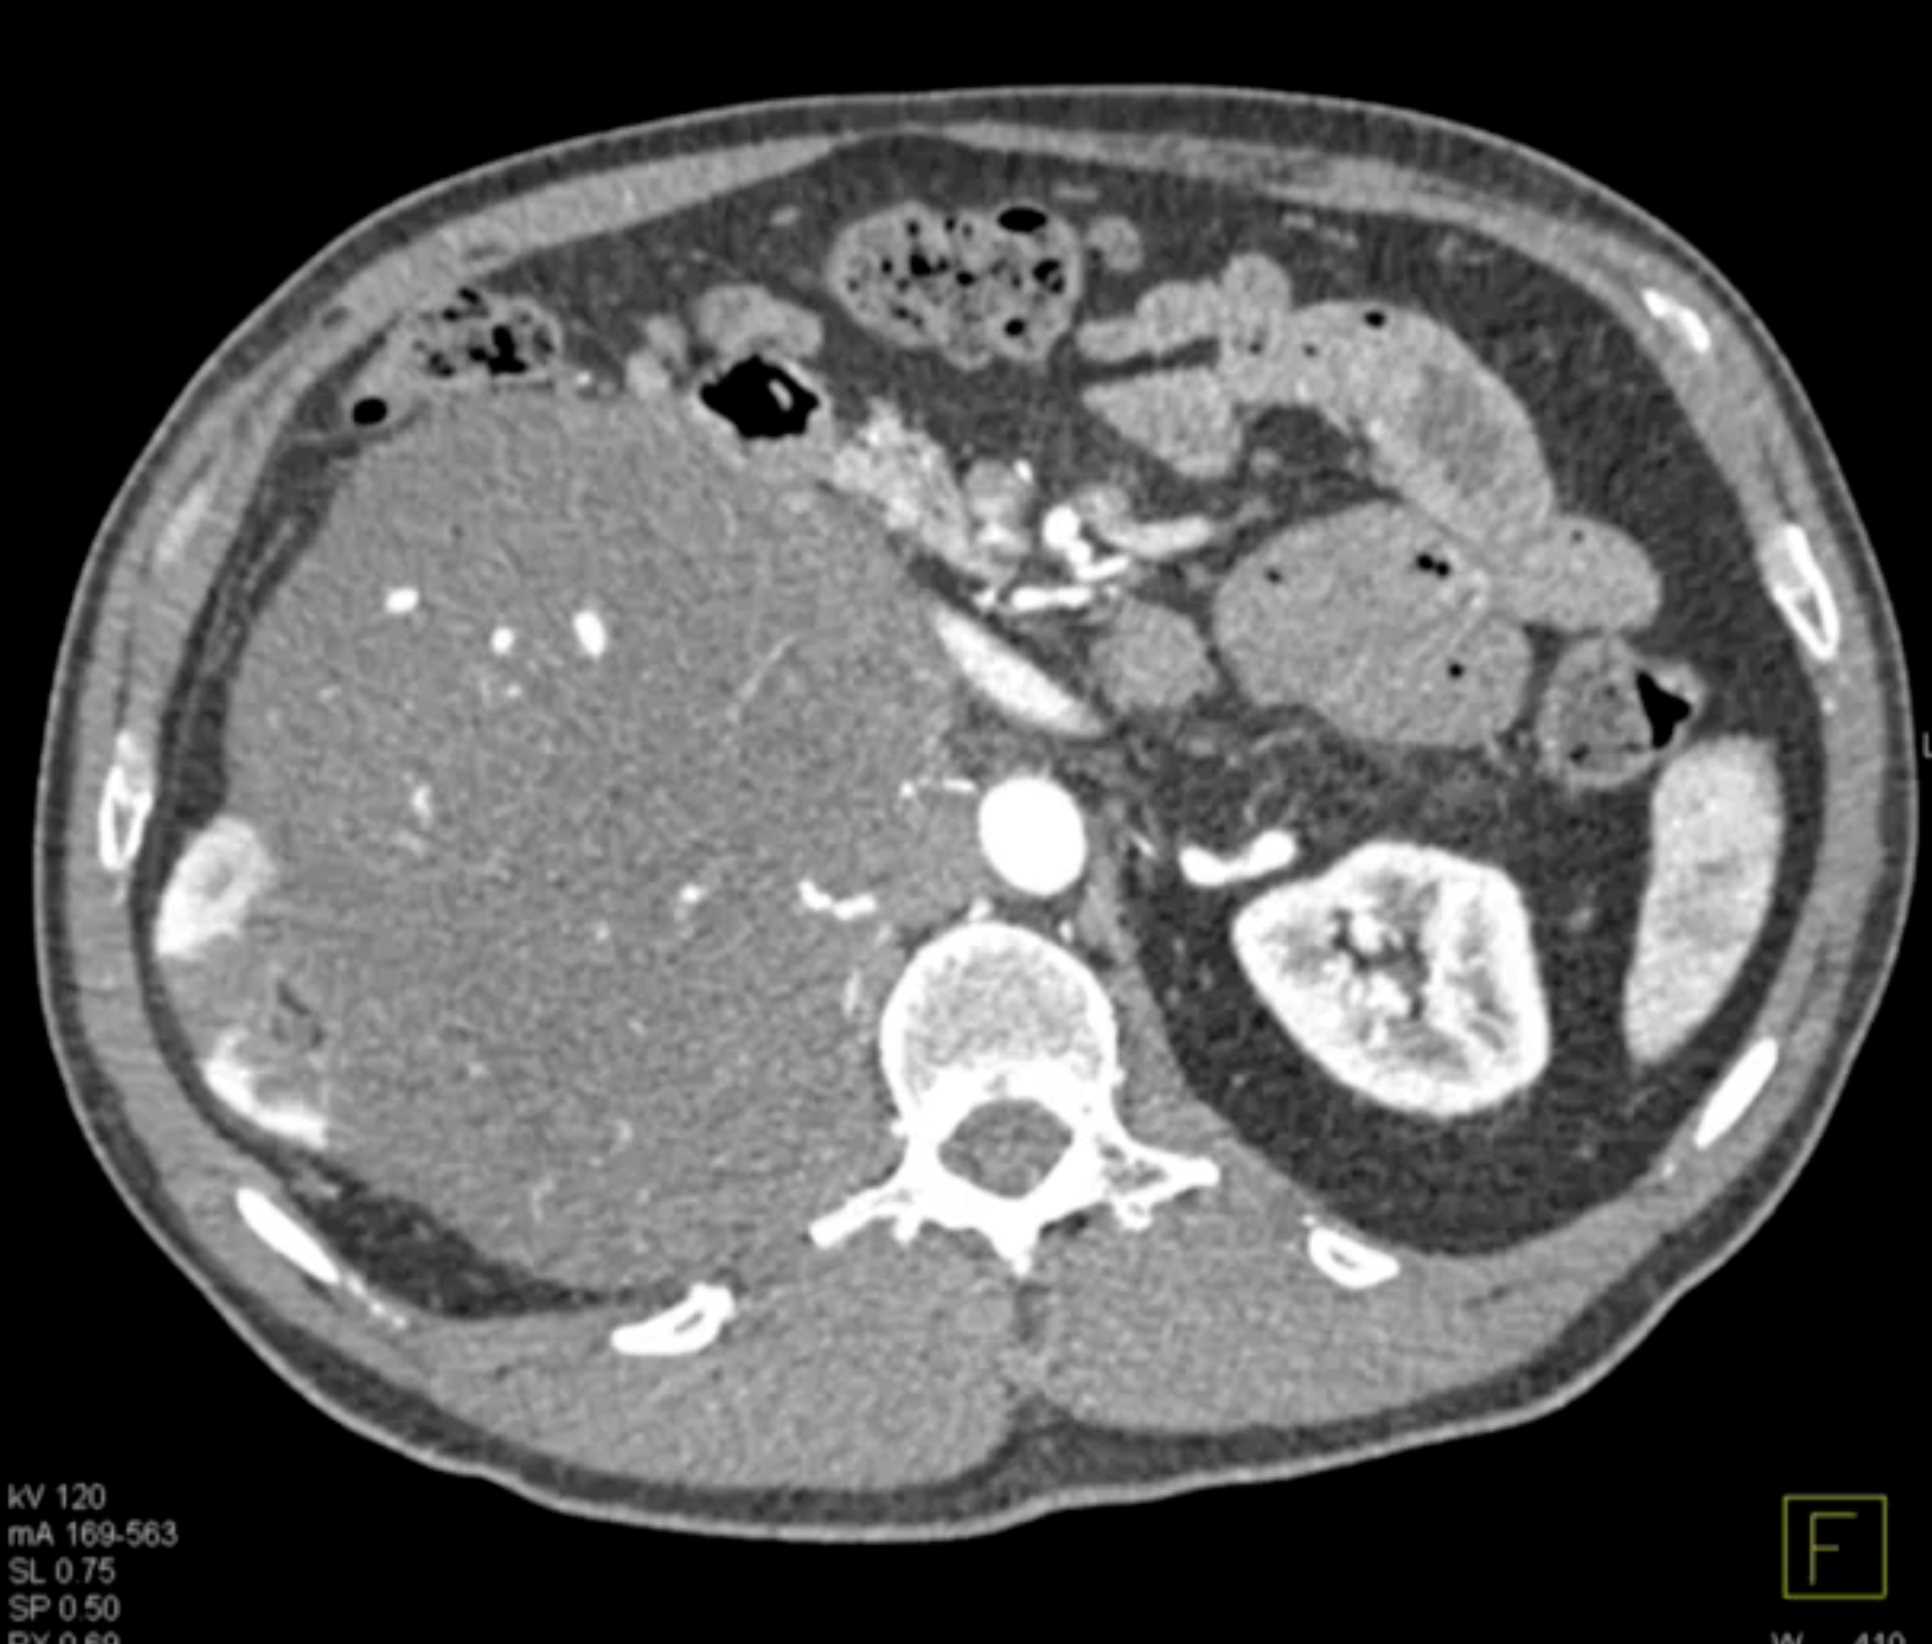

Left Adrenal Metastases from Renal Cell Carcinoma